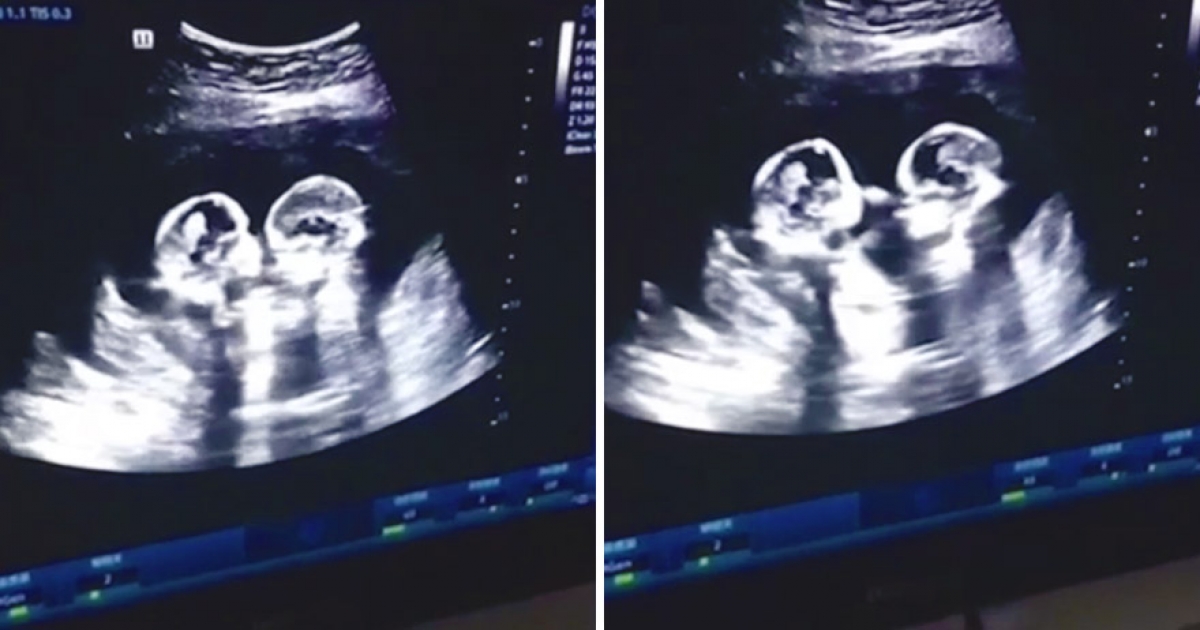

還在子宮裡就已經「爭寵」! 雙胞胎姊妹的「小手手互動」讓醫生和爸媽都笑哭